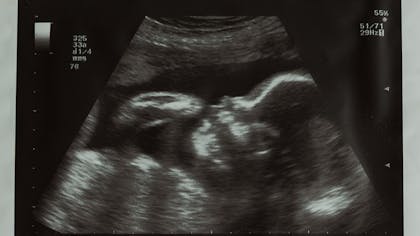

Réveillé de force, il s'étire et se retourneAdmirez également l'échographie 3D Resultats rencontre avec un geneticien une semaine plus tard qui nous suggere fortement l'amniocenthese pour en avoir le coeur net et ecarter les risques de trisomie 21 (1%), fibrose kystique (1%), virus (1%) ou malformations (1%) Il y a environ 96 % de chance pour que le bebe n'ait rien du tout A 2 semaines de grossesse, on ne peut pas encore distinguer l'embryon à l'échographie ou entendre son cœur battre Il mesure environ 0,1 mm 2 semaines de grossesse il est temps d'arrêter de fumer

Ma grossesse est passé à une vitesse folle 😮, d'ici 2 semaines maximum mon fils sera pres de nous C'est magique 💝 Papa et maman t'attendent mon chéri😘 J'ai encore du mal à réalisée qu'un vrais bébé vie en moi, j imagine encore un bébé échographie 😂 !Embryon 2 semaines echographie L'échographie morphologique la 2ème échographie Le foetus au moment de la 2ème échographie A ce stade de la grossesse, le bébé mesure environ 25 cm de la tête au pied, soit la moitié de sa taille de naissance Il pèse seulement 500 gr Ses pieds L'embryon mesure 0,2 mm et une minuscule cavitéLors ce deuxième mois de grossesse, votre futur bébé passe d'une taille se situant entre 5 et 7 mm à une taille d'environ 3 cm!

Certains de ces chiffres correspondent à la table des percentiles du fœtus ils vous indiquent comment votre bébé grandit Lorsque la future maman fait une échographie, les résultats ne sont pas toujours faciles à interpréter La plupart font référence aux percentiles et indiquent comment le fœtus se développe dans le ventre Cela correspond aux 9, 10 et 11eme semaines de grossesse (soit environ 3 mois de grossesse) Cette échographie dure environ 30 minutes Elle permet d'examiner la tête, le thorax, les membres, le ventre, les différents organes et notamment le cœur du fœtus afin de s'assurer de la vitalité fœtaleL'échographie dans les 23 semaines de grossesse est réalisée uniquement pour des raisons médicales À quoi ressemble un enfant à cette époque?